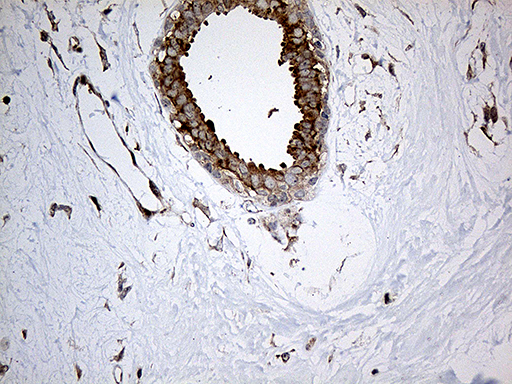

Facts about Interleukin-34.

Plays an essential role in the regulation of osteoclast proliferation and differentiation, and in the regulation of bone resorption. Signaling through CSF1R and its downstream effectors stimulates phosphorylation of MAPK1/ERK2 AND MAPK3/ERK1 (By similarity).